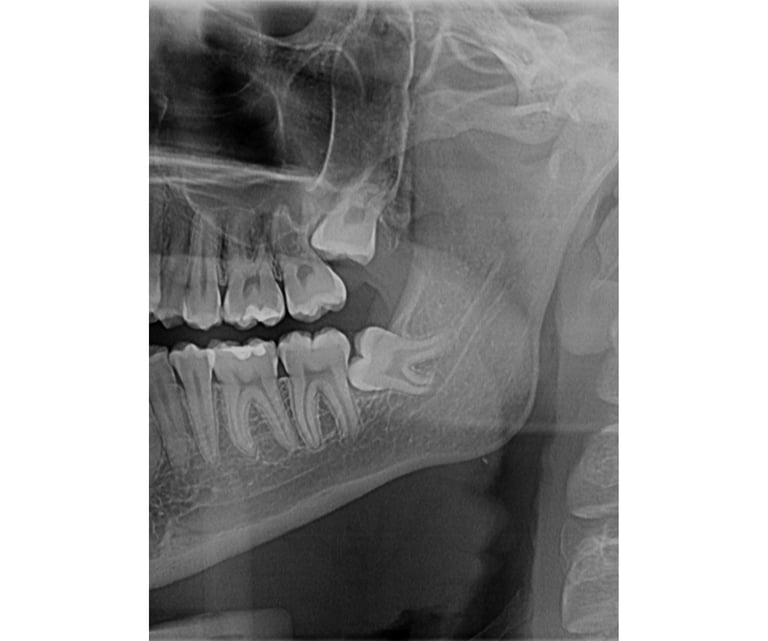

Impaktirani umnjaci su treći stalni molari koji često ne mogu da izniknu te ih je neophodno odstraniti.

Impaktirani umnjaci su treći stalni molari koji često ne mogu da izniknu te ih je neophodno odstraniti.Hirurška ekstrakcija je rutinska oralnohirurška intervencija koja se izvodi u lokalnoj anesteziji. Naš tim se trudi da ova intervencija prođe što bezbolnije i sa manjim otokom.Pre i posle intervencije ćete dobiti sve neophodne savete. Za jako plašljive, postoji mogućnost sedacije azot-suboksidom radi oslobađanja straha.